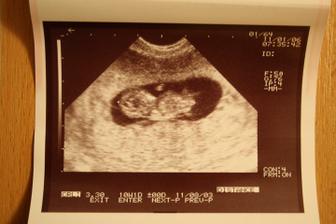

6.1.2011 třetí kontrola (11tt) - dostali jsme těhu průkajdu, byli jsme na odběru krve, vyšetření moči a dostali jsme tři ultrazvuky. Mimísek měří 33mm